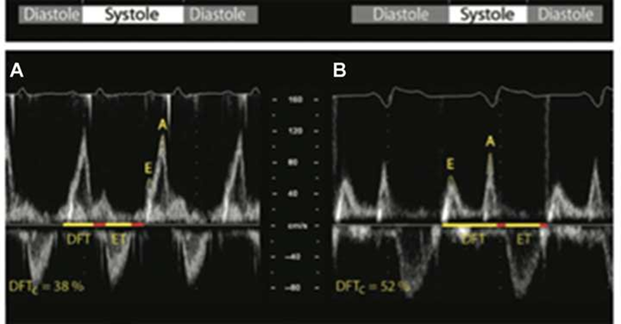

3. AVS: when the best diastolic filling was verified under long native PRi (visually separated E and A waves, their sum exceeded 40% of the cardiac cycle (Figure 2)).1,7

Figure 2 Optimal AV interval (oAVi) is defined when allowing the completion of the atrial contribution to diastolic filling (diastolic filling time [DFT], which should last for at least 40% of the cardiac cycle). The oAVi results in a more favourable preload before ventricular contraction, with minimal mitral regurgitation.

Left: AV dyssynchrony (A), shown by fused and almost superposed E and A waves at Doppler transmitral flow, determining their sum to result in suboptimal DFT (38%), not allowing the conclusion of the atrial contribution to ventricular.

Right: oAVi (B), the sum of E and A wave durations spans 52% of the cardiac cycle, resulting in favourable preload before ventricular contraction [1]. DFTc, DFT corrected for RR interval; ET, ventricular ejection time; E and A, waves at Doppler transmitral flow.